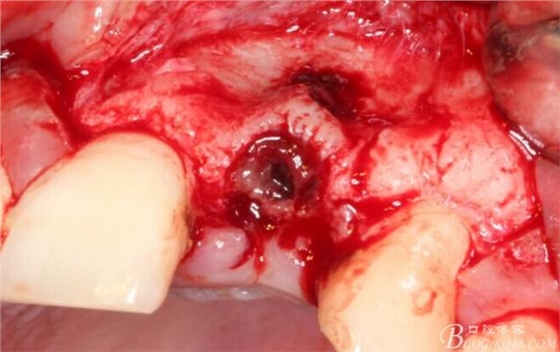

于是我果斷告知患者,手術(shù)失敗了,不能拖延,如不及時處理,炎癥繼續(xù)發(fā)展會很快波及鄰牙牙槽骨。患者接受我的建議。切開翻瓣,骨粉及生物膜消失了,骨吸收嚴(yán)重,幸運的是,因為處理及時,鄰牙骨支持依然存在。

徹底掻刮。